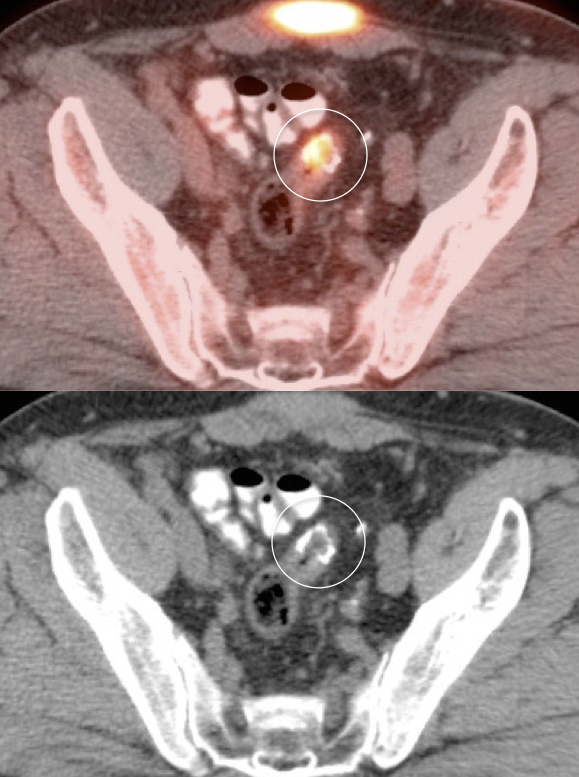

Value of Non-Attenuation Corrected (NAC) Images

Resolving Attenuation Correction Artifacts:

The CT images obtained during an exam are not only used for “anatomic” interpretation. They are also used for “attenuation correction” (AC) of the PET images, generating the much more useful AC PET images used for interpretation.

Unfortunately, attenuation correction of PET images can result in falsely elevated metabolic activity in regions of high CT density (e.g. metallic devices, oral contrast, calcification).

In such cases, these areas must be reviewed on the NAC (non-attenuation correction) images. If these regions are not also hypermetabolic on the NAC images, then their apparent increased FDG-uptake on the AC images is artefactual.